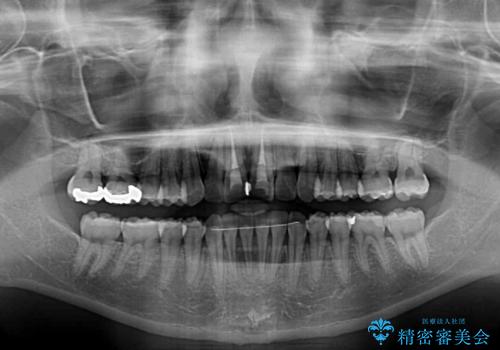

- 前歯の著しい叢生と前突感を気にして来院された患者様です。

叢生が強いため、事前に前歯をワイヤー矯正で速やかに叢生を解消し、その後はインビザラインにて矯正治療を行うこととしました。

ワイヤー矯正を併用したことで前歯の叢生を速やかに解消することができました。

一方口元の突出感を改善するために時間がかかり、2年超を要しましたが、満足のいく仕上がりとなりました。